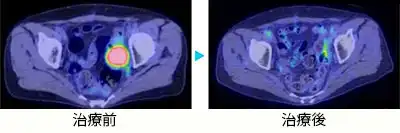

- 卵巣がん骨盤内再発 70代女性

- 卵巣がん骨盤内転移

卵巣がん骨盤内再発 70代女性

卵巣がん骨盤内転移